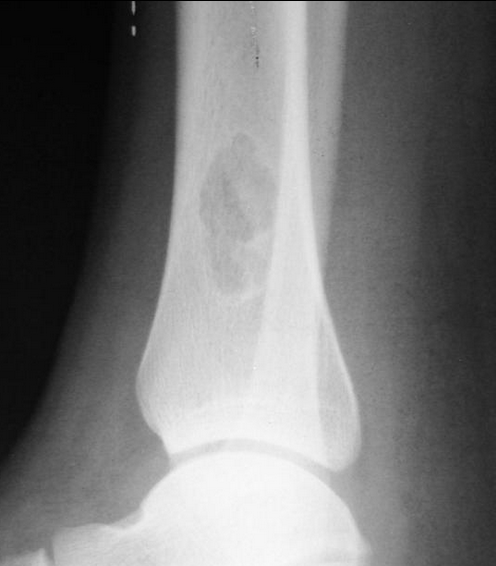

Fibroxanthoma

• Well-defined, eccentric, bubbly lucent lesion in the metaphysis of a child with deep sclerotic margin, overlying cortical interruption, and no periosteal reaction are essentially diagnostic of a fibroxanthoma (or nonossifying fibroma). The mixed signal of the lesion on MR is also typical of a fibroxanthoma.